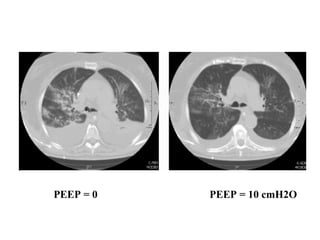

Recrutement alvéolaire

=

Application d’une PEEP externe

• Ouverture d'alvéoles préalablement collabées

• Ré-aération de territoires pulmonaires condensés ++

PEEP = 0 PEEP = 10 cmH2O

• PEEP ≥ 5 cmH20